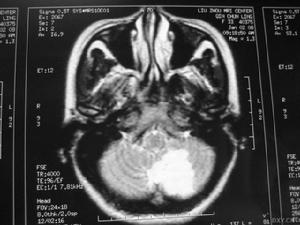

主要表現為頭痛、嘔吐、視乳頭水腫、癱瘓、部分性運動性癲癇發作等,常伴不同程度的意識障礙。這些雖然擬似顱內占位病變的症狀,但起病急,病情迅速加重,從起病至症狀頂點短者僅數小時,多數均在一個月內;顱內壓急劇增高,部分患者可迅速出現顱內壓增高危象;頭顱CT和MRI檢查均可見彌散性腦水腫和腦軟化區等,均有助與腦瘤鑑別,但確診有時需依賴開顱探查或立體定向鑽孔穿刺進行腦組織活檢。

4、顱腦CT可見腦內大小不等、邊界不清的低密度灶。

5、放射學檢查:常規頭顱放射學檢查對散發性腦炎的診斷無重要價值。頭顱CT有時可見大腦半球多個散在的軟化灶,對排除占位性病變有一定意義。